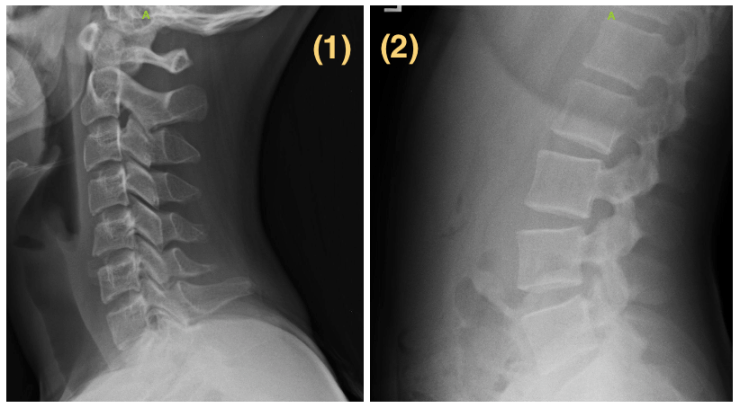

Here are the two images I showed them. Image #1 is the side view of her neck. Image #2 is the side view of her lower back:

Without any hesitation, all nine of the doctors guessed that the patient in image #1 was in their mid-40’s. Their guesses for image #2 varied slightly, but were in the same ballpark, ranging from “adolescent” and “college student” to “no older than 25.”

After collecting all of their answers, I revealed to them that these images belonged to the same person. Each of them expressed concern after hearing this news. It’s troubling to see someone this young with a spine that looks so “old” (relatively speaking).

I decided to get some additional perspective; this time from a pediatrician who works at an award-winning pediatric hospital. The doctor, who admittedly has limited experience evaluating spinal X-rays, was surprised and intrigued that a teenager could have such noticeable structural changes, and showed concern about the level of pain this young girl may have by the time she reaches 25-30, if left untreated.